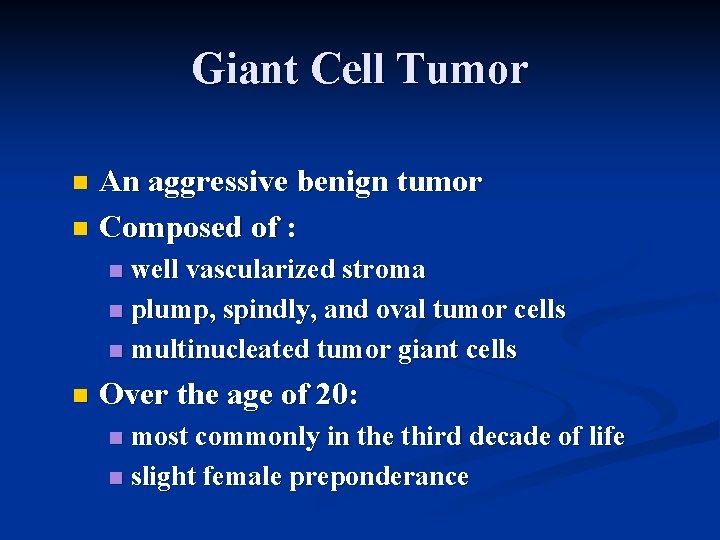

Giant Cell Tumor An aggressive benign tumor n Composed of : n well vascularized stroma n plump, spindly, and oval tumor cells n multinucleated tumor giant cells n n Over the age of 20: most commonly in the third decade of life n slight female preponderance n